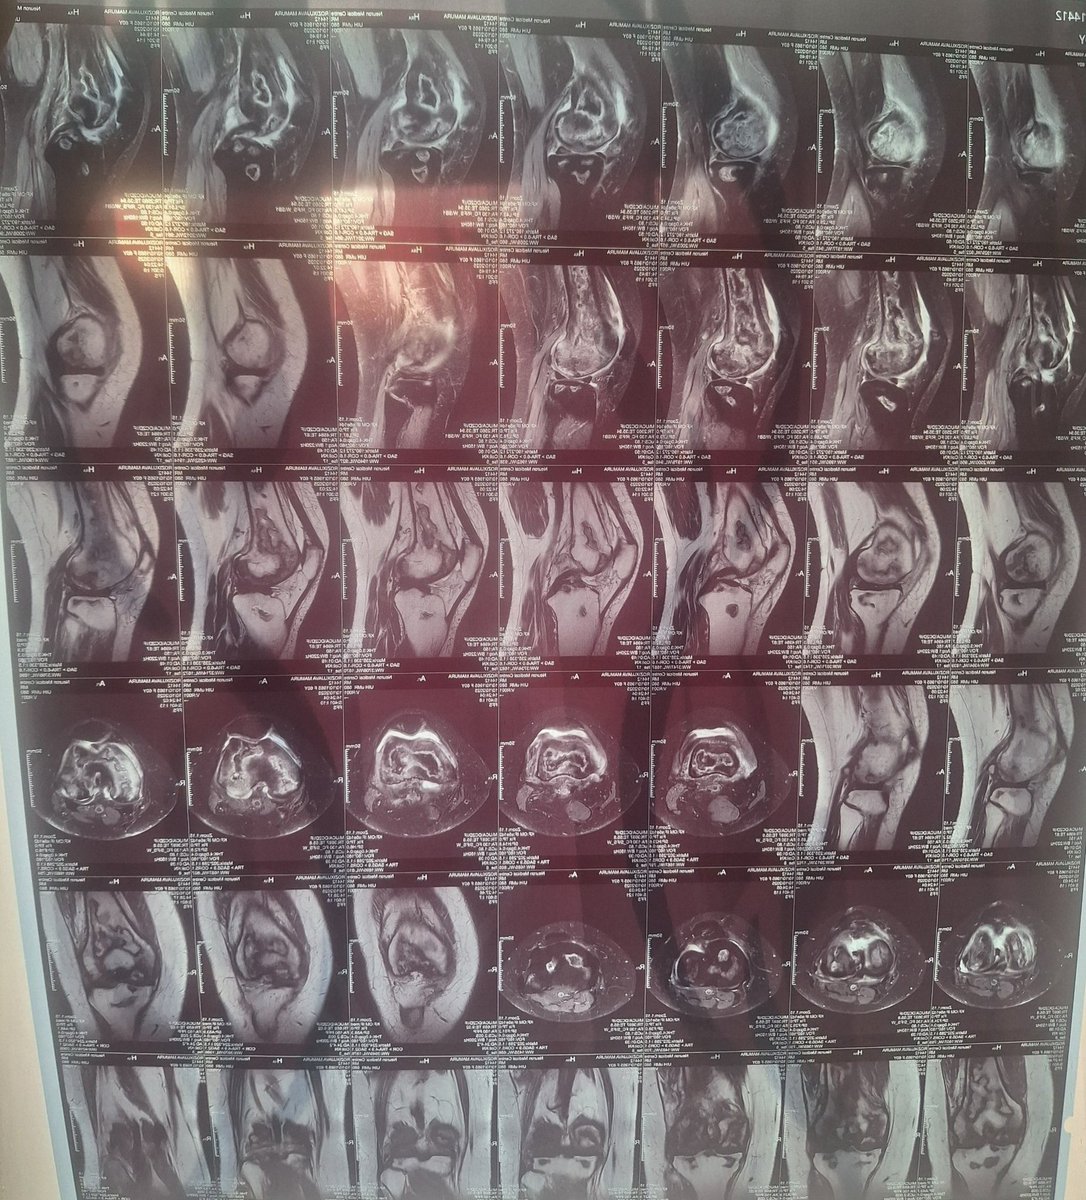

Қибрайлик Маъпура опанинг тизза соҳаси операция қилинганди. Айни пайтда суяк тўлиқ битмаган. Ҳозирда у яна даволаниши зарур. Карта рақамлари: 8600 0610 7755 4755 5614 6816 2082 6382 Розиходжаева Мапура номида

Қибрайлик Маъпура опанинг тизза соҳаси операция қилинганди.

Айни пайтда суяк тўлиқ битмаган.

Ҳозирда у яна даволаниши зарур.